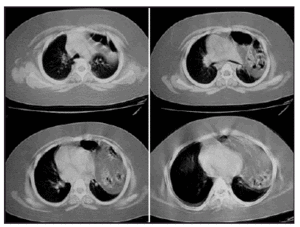

Radiografía de tórax: imagen de condensación que ocupa la mayor parte de hemitórax izquierdo (fig. 1). TC torácica: ocupación del hemitórax por contenido intestinal en región anterior que se extiende hasta ápice pulmonar (fig. 2). Diagnóstico: hernia de Morgagni de presentación tardía y hallazgo casual. Actualmente nuestra paciente está asintomática desde el punto de vista respiratorio y a la espera de la intervención quirúrgica.

Figura 2. TC torácica. Ocupación del hemitórax por contenido intestinal en región anterior del tórax, que se extiende desde las bases pulmonares hasta el vértice pulmonar.